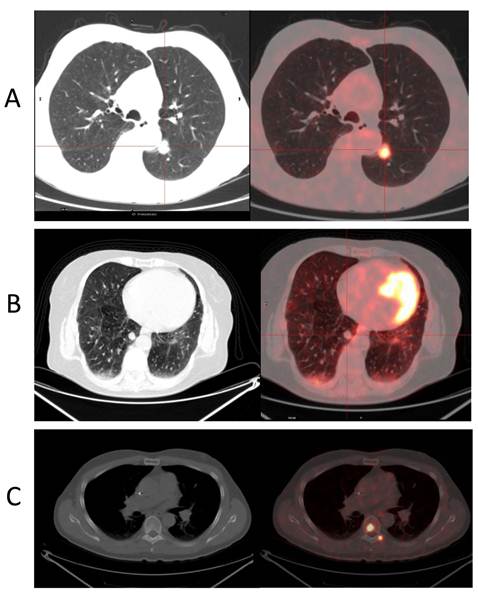

There are several examples of specific tracers already in clinical use. Figure 4 shows [11C]-5-hydroxytryptophan uptake in two very small bone metastases in a patient with a known carcinoid tumor. 5-Hydroxytryptophan is the precursor of serotonin. The converting enzyme 5-hydroxytryptophan decarboxylase is highly expressed in the majority of tumors with neuroendocrine origin.[20] After evaluating more than 1000 patient scans, it has been confirmed that no other tumor type or pathological process have any extensive expression of the enzyme. As such, focal uptake of this tracer in the bones can only be explained by metastases from a neuroendocrine tumor. With experience, a tool like this sometimes obviates the need for additional histopathology and the referring doctor moves directly towards relevant therapy.

Figure 4

A sagittal [11C]-5-Hydroxytryptophan PET/CT sectioning the spine in a patient referred for follow-up after treatment for a carcinoid tumor. Because of the specificity of the tracer, the very intense uptake in the millimeter-sized spinal lesions is highly suspicious for bone metastasis.